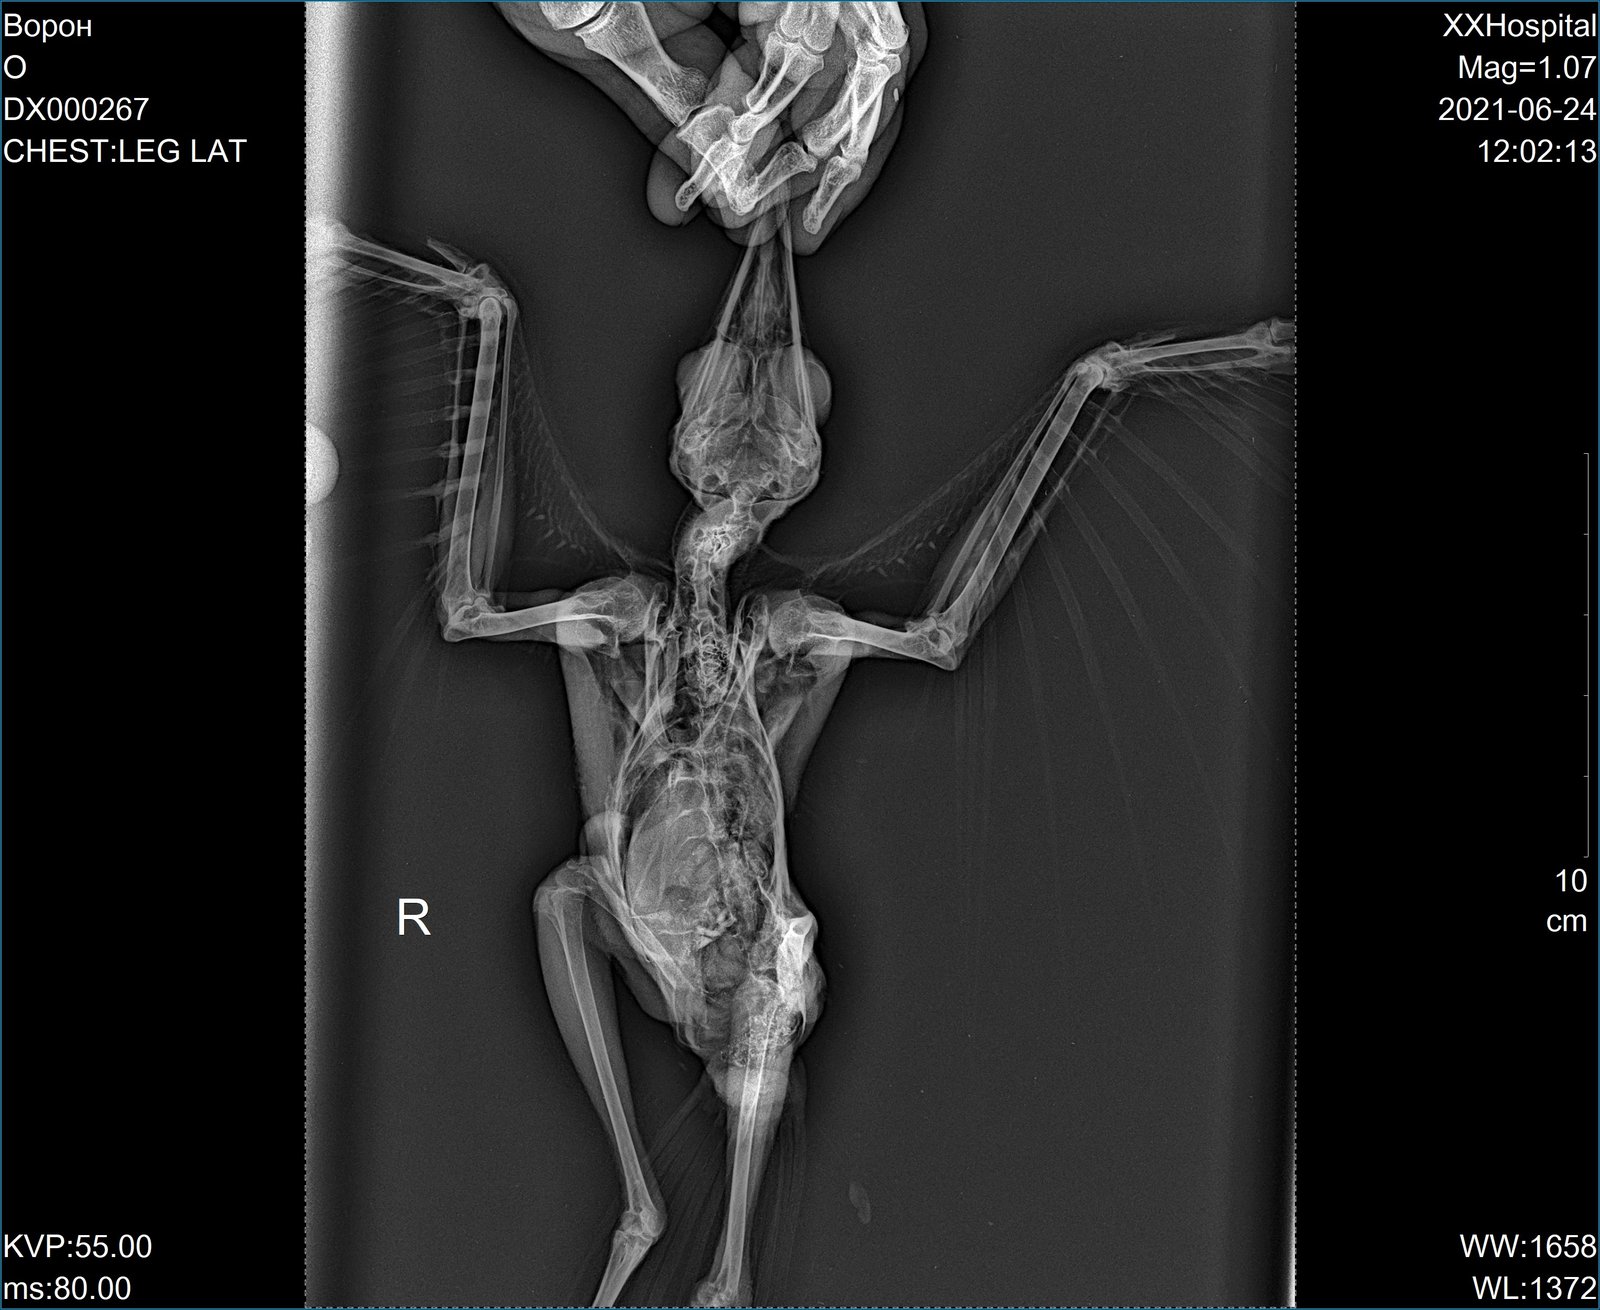

olegru100 Опубликовано 24 июня, 2021 #13 Опубликовано 24 июня, 2021 (изменено) Выкладываем выписку и рентген: На осмотре: - отсутствует чувствительность к боли обоих лап ( мед. иглой). Рентген: - множ. перелом тазобедренной кости, есть осколок (вроде так сказал хирург, он же делал рентген). С позвоночником неясно или не сказали (будут консультироваться с Полиной Юрьевной - до субботы решат). Полина Юрьевна сама не принимает - в декретном отпуске. Назначения в выписке, как я понял, только обезбаливающие. Ждем мнение и назначение медикаментов от врачей форума (пожалуйста направьте спецов в эту тему). Когда вороненок на руках - правую лапу поджимает к телу, левая - висит, но когда ладонью поджимают лапы ( как бы садят на ладонь) левая лапа тоже поджимается как бы правильно, крыльями машет - это все на осмотре. Изменено 24 июня, 2021 пользователем olegru100 измение 1

Набежда Опубликовано 24 июня, 2021 Автор #17 Опубликовано 24 июня, 2021 @With Hooded CrowОчень надеемся, что спасти получиться ребёнка. Только что-то про позвоночник хирург сказал (не поняли мы). Вроде тоже повреждение и лапки обе не работают. До субботы должны заключение сделать в клинике. @With Hooded Crow 1

Набежда Опубликовано 24 июня, 2021 Автор #18 Опубликовано 24 июня, 2021 @With Hooded Crow Да, врачи сказали что бывает, самовосстанавливаются при травме позвоночника. Но вот с ногой, совсем плохо. Но ещё заключительного вывода от врачей нет. Ещё один врач посмотреть снимки должен. @With Hooded Crow

Набежда Опубликовано 24 июня, 2021 Автор #29 Опубликовано 24 июня, 2021 @With Hooded Crow К сожалению у него не только серьёзные травмы, но и не возможность сделать операцию, я не могу объяснить, но как сказали врачи что косточки у него светятся и операцию нет возможности сделать. И еще, они что-то объясняли, но я от волнения забыла. А насчёт динамики, очень ухудшилось его состояние за 10 дней. 1